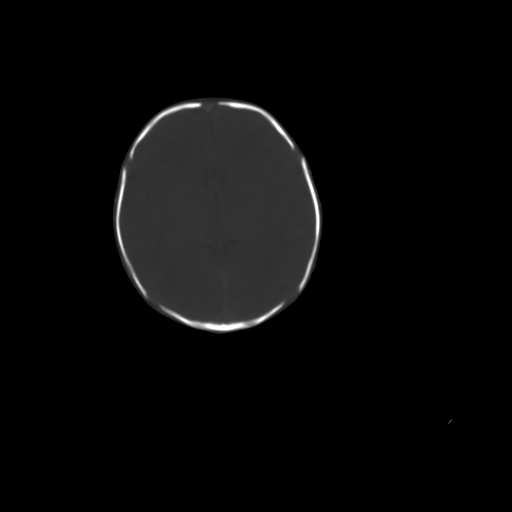

男,12天,自然分娩,其母发现右顶部头皮包块逐渐增大。

右顶部头皮血肿

右顶部头颅血肿(骨膜下血肿)

右顶部头皮血肿。

右顶部头皮血肿,可能是产道挤压所致。以后会慢慢恢复。

疑问:患儿脑白质密度比较低,基底节区密度比较高,类似于“双圈征”脑沟密度也偏高。该婴儿可有别的异常吗?反射正常吗?评分能达到5分吗?如果正常,就随诊观察吧。不正常要考虑到缺血缺氧性脑病。